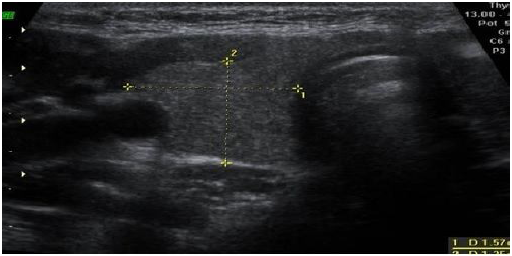

Se completó estudio con ecografía tiroidea que demostró la presencia de 2 nódulos sólidos en el lóbulo tiroideo derecho, el primero de ellos de 5 mm con calcificaciones groseras en su interior, y el segundo localizado en su porción inferior, de 6 mm de diámetro hipoecoico. Se observaron también múltiples adenopatías de aspecto patológico en cadena laterocervical derecha, una de ellas de 16 mm de aspecto necrótico quístico (Figura 1). En el compartimento laterocervical y hueco supraclavicular izquierdo se observaron imágenes ganglionares hipoecoicas de tamaño no significativo.